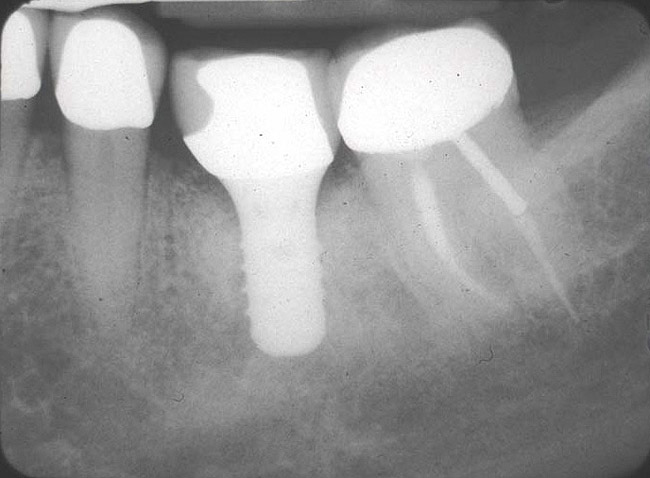

Figure 7  Following removal of a mandibular first molar an osteotomy was performed in the interradicular bone, a guide pin placed, and a radiograph taken.

Figure 7

Figure 8  A straight-walled implant with a 4.8-mm diameter and a 6.5-mm restorative platform diameter has been placed in the interradicular bone following tooth sectioning and removal. Primary stability has been attained.

Figure 8

Figure 9: Following manipulation of the interradicular bone, implant placement, and performance of concomitant regenerative therapy, the hard tissues are mature and the implant is ready for restoration.

Figure 9

Figure 10  A radiograph taken 54 months after implant restoration demonstrates the stability of the crestal peri-implant bone.

Figure 10